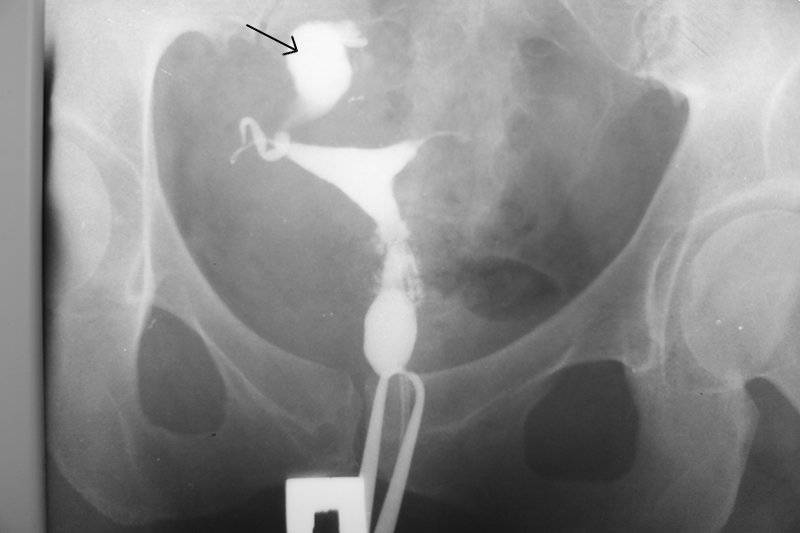

Медицинские снимки: Проходимость маточных труб

Раздел: Кадры-подсказки